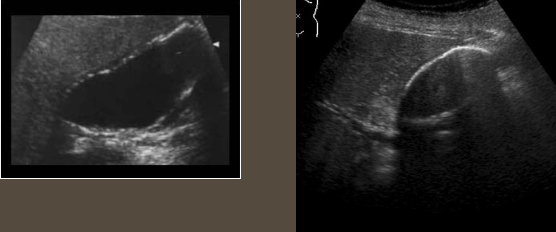

Hydropic Gallbladder → distended GB

clinical hx: middle-aged to older, fasting, post-surgery

s/sx: asymptomatic, if not = RUQ pain, fullness/bloating

2D US: no relaxed curves, rounded/bulbous shape, ± distended cystic duct (check for obstruction), maintained thin wall

color doppler: avascular

DDX: acute cholecystitis, cholelithiasis